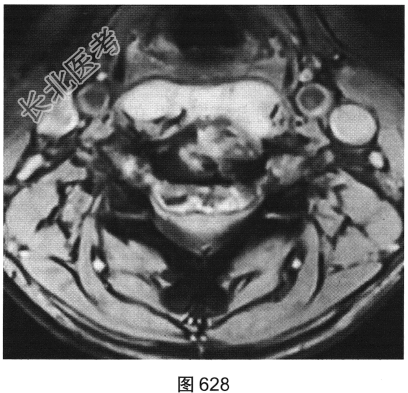

- [材料题] 患者男性,34岁,近数月乏力,偶有低热。颈部疼痛2个月余,逐渐加重,有轻压痛,颈部活动受限。

- 多项选择题2.[提示]患者行颈椎X线、CT和MRI检查,见图623~图628。首先应考虑患者为下列哪种疾病( )